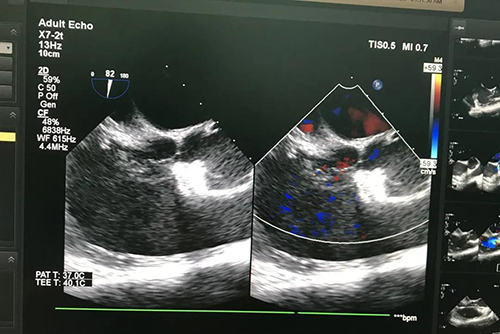

在王安彪主任医师指导下,东院心外科主任医师訾捷操作,李鹏飞主治医师协助开展手术,超声诊疗科郭文斌主任进行超声引导,麻醉手术科王岩主任医师、主治医师孙伟、赵金阳等进行麻醉操作。手术开始前,食道超声再次探查确认患者主动脉右冠窦瘤破裂,二叶式主动脉瓣,破口基底部位于右冠窦偏右侧,大小约0.9cm,窦瘤凸入右心房,其上有两处破裂口。在超声引导下,訾捷主任医师自右侧股动脉穿刺点将导丝逆行送入主动脉窦瘤破口的右心房一侧;继而将12mm的封堵伞装入输送鞘,超声引导下依次精确推送出两个伞盘,经推拉试验确认封堵伞卡位牢固,超声检查无残余分流,对主动脉瓣无影响。手术顺利完成,整个手术过程耗时不到1小时,胎心监测全程无明显波动。

患者术后第2天复查,心脏彩超显示封堵器位置固定,主动脉窦水平无异常分流,主动脉瓣无返流;胎儿心脏超声亦未见明显异常。由于该手术创伤极小(仅右侧腹股沟有一穿刺点),术后除小剂量阿司匹林抗凝外无需其他任何治疗。该患者已于复查当日顺利出院。